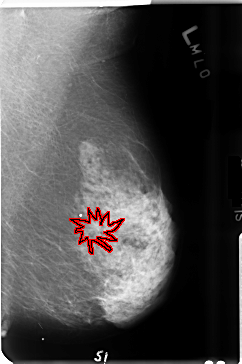

B_3514_1.LEFT_MLO

LEFT_MLO LINES 4720 PIXELS_PER_LINE 3144 BITS_PER_PIXEL 12 RESOLUTION 50 OVERLAY

FILE: B_3514_1.LEFT_MLO.OVERLAY

TOTAL_ABNORMALITIES 1

ABNORMALITY 1

LESION_TYPE MASS SHAPE ARCHITECTURAL_DISTORTION MARGINS ILL_DEFINED

ASSESSMENT 4

SUBTLETY 3

PATHOLOGY MALIGNANT

TOTAL_OUTLINES 1

BOUNDARY